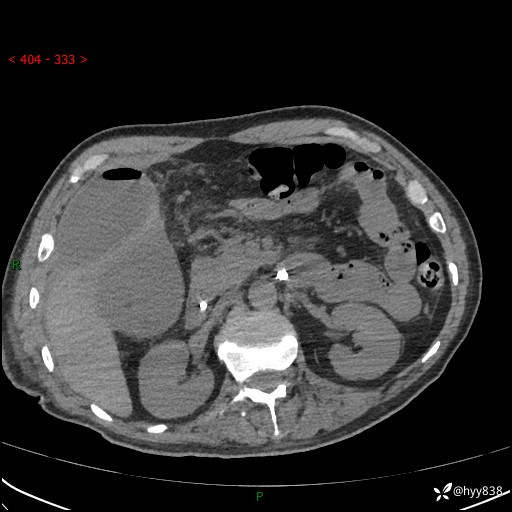

腹部CT平扫

增强